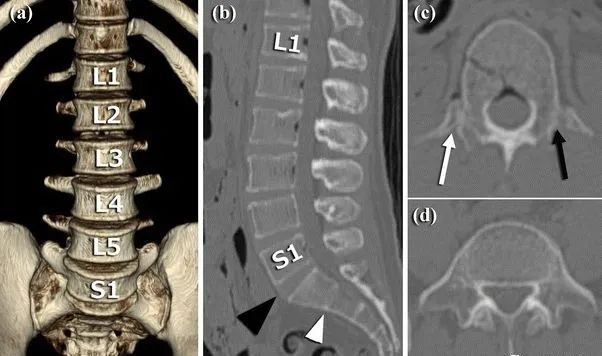

1984年,Castellvi提出LSTV分类系统将移行椎分为Ⅰ-Ⅳ型。

Ia型(单侧)和Ib型(双侧):横突肥大宽度超过19mm

IIa型(单侧)和IIb型(双侧):横突与骶骨相接触形成假关节

IIIa型(单侧)和IIIb型(双侧),横突与骶骨发生骨性融合

IV型:一侧横突与骶骨形成假关节,另一侧形成骨性融合

目前,腰骶移行椎以Castellvi的分类方法最为常用。其主要根据横突形态及其与骶骨、髂骨是否融合或形成假关节而分为4型,Ⅰ、Ⅱ、Ⅲ型又根据单、双侧分为A、B两个亚型。

正常

I型:主要为腰5横突发育不良,横突宽度大于19mm,并将其分为两个亚型Ia(单侧横突发育不良)或Ib(双侧横突发育不良)

L5右侧横突肥大,为Ⅰa型

L5双侧横突肥大,为Ⅰb型

II型:表现为不完全的腰椎骶化,具有增宽的横突,并且和骶骨形成假关节,并将其分为两个亚型IIa(单侧关节形成)或IIb(双侧关节形成)

L5左侧横突肥大,假关节形成,为Ⅱa型

L5双侧横突肥大,假关节形成,为Ⅱb型

III型:单侧(IIIa)或双侧(IIIb)腰椎完全骶化,腰5横突与骶骨完全骨性融合

L5右侧横突肥大与骶骨发生骨性融合,为Ⅲa型

L5双侧横突与骶骨骨性融合,为Ⅲb型

IV型:一侧为II型即腰5横突与骶骨形成假关节,对侧为III型即腰5横突与骶骨形成骨性融合

IV型即混合型:L5双侧横突肥大,一侧与骶骨相接触为Ⅱ型表现,另一侧与骶骨形成骨性融合为Ⅲ型